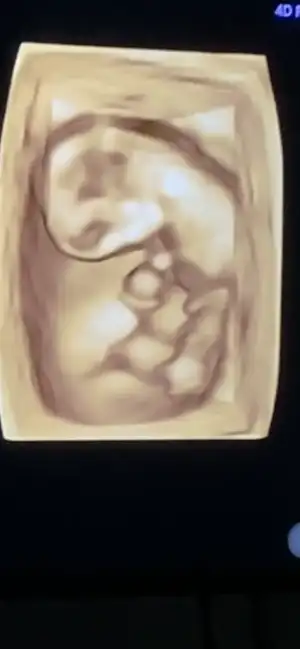

Kızlar merhaba doktorumu değiştirme kararı aldım ikili testimi devlette yaptırmıştım sonucunu göstermek istedim tersledi beni kibarca kovulduk gibi oldu😂 bakmayın gülüyorum ama çok içerlendim yani çalıştığım hastanenin imkanlarımı kullanmam çok mu saçma anlamadım. Eşim çok sinirlendi paranız mı yok gibi bir muhabbet döndü. Bilmiyorum inşallah içime sinen bir doktor bulabilirim😊 %80 erkek dedi bakın bu da üç boyutlu halimiz galiba pipimiz gözüküyor çok hareketliymiş